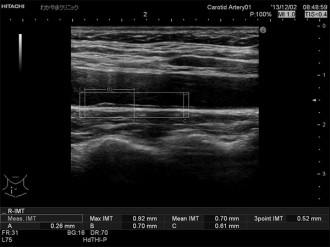

第1層と第2層を内中膜複合体(IMC)と呼び、その厚さを計ります。

IMCの厚さは通常1mm未満です。1mmを超えると動脈硬化が示唆されます。

IMCは加齢と共に肥厚します。高血圧、脂質異常症、糖尿病、肥満などはIMC肥厚を加速させる危険因子です。